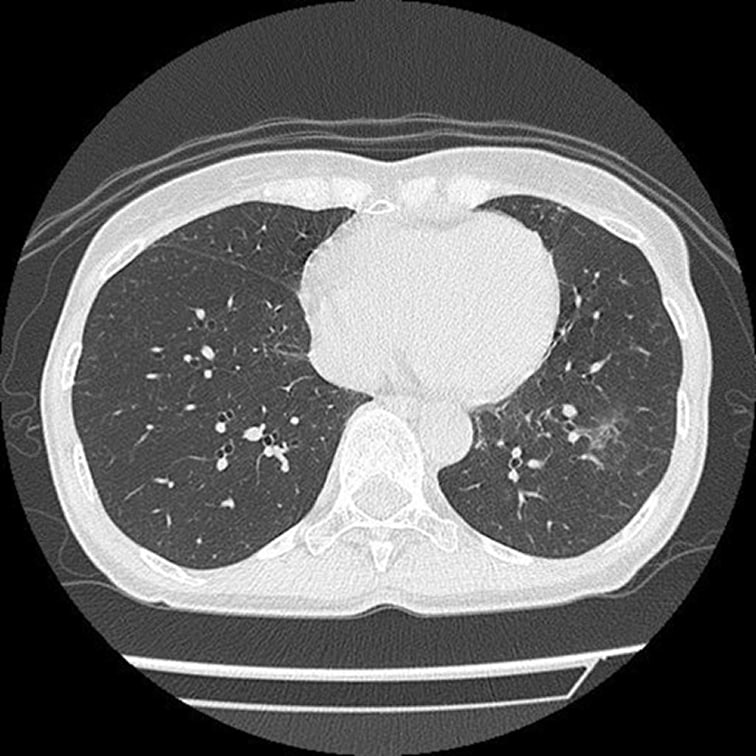

低線量CT

* 低線量CTについて

通常のCTに比べ、被検査者に与える被ばく量を軽減することが可能です。一方、撮影される画像は、通常のCTに比べて質が低下する傾向にあり、読影診断の難易度が高まると言われています。